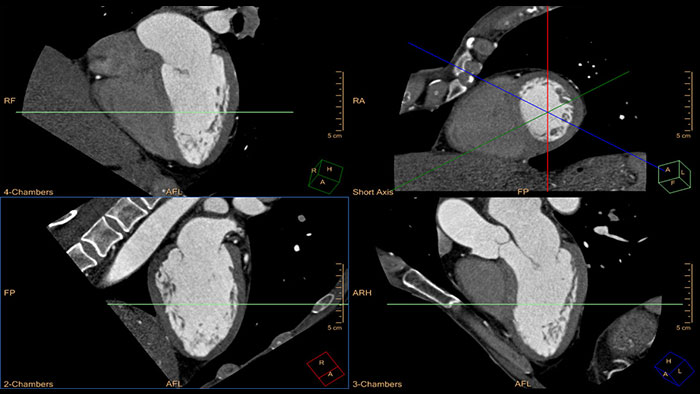

Quick cardiac visualization

Provides a set of tools for the visualization of one or multiple cardiac phases using original images or MPR\MIP images in axial, coronal, sagittal or dedicated cardiac axes (short axis, horizontal long axis, and vertical long axis).

Comprehensive cardiac analysis

Designed to assist the user in viewing, analyzing and quantifying dedicated Cardiac CT Angiograms, mainly for coronary arteries analysis on Coronaries CT Angiogram (CCTA) data.